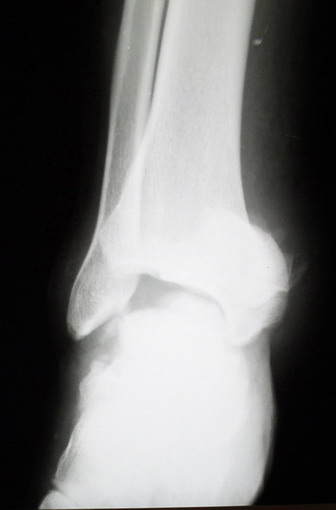

Среди повреждений таранной кости (Hawkins III-IV) с одновременной травмой лодыжек встретилось следующее (см. вложение). Пациент упал в колодец на глубину 10 метров (Х.2002 г.), госпитализирован с диагнозом: з/перелом шейки правой таранной кости (Hawkins IV) с переломовывихом тела назад и кнутри, закрытый перелом внутренней лодыжки и переднего края большеберцовой кости. Оперирован в первые 12 часов после травмы, выполнена открытая репозиция таранной кости, внутренним и передне-внутренними доступами, остеосинтез переломов шейки и тела губчатыми винтами, для реваскуляризации тела таранной кости первичный компрессионный над- и подтаранный артродез. Синтез внутренней лодыжки губчатым винтом. Удаление винтов через 1 год,2 мес. Получен анкилоз указанных суставов с сохранением длины конечности, полная реваскуляризация таранной кости, о чем говорит сращение ее переломов, отсутствие отеков и

цианоза стопы и голени. Компенсаторная подвижность переднего и среднего отделов стопы около 15-20 градусов за счет поперечного (Шопара) сустава стопы. Считаю оправданной подобную тактику, не смотря на угрожаемый прогноз (100% асептический некроз) по классифицкации Hawkins.